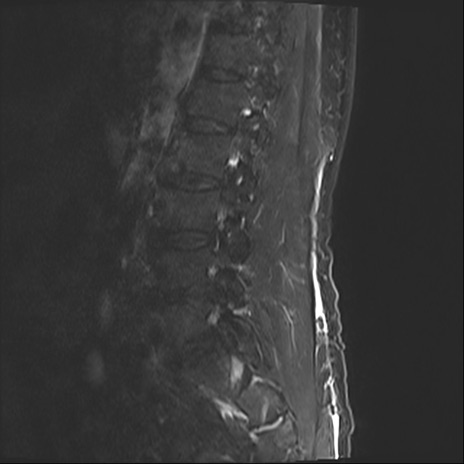

【整形】TIPS症例2 腰椎MRI STIR(矢状断像)

【症例】70歳代男性

【主訴】左下肢痛

【現病歴】2週間前くらいから腰痛、左下肢痛あり。左臀部から大腿、下腿外側のしびれが常時ある。歩行とともに同部位の痛みあり。

【身体所見】Lasegue70-/60+、Bragard-/±、PTR ±/±、ATR -/-、IP 5/5、TA 5/4、TS 5/5、EHL 右第1足趾なし/3、FHL 5/5、hypersthesia(-)、足背動脈触知良好

異常所見と診断は?